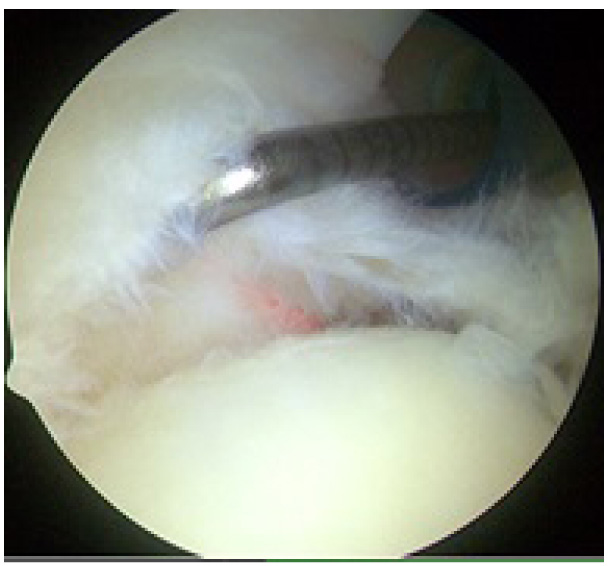

Fig. (2) Right shoulder with the patient in the lateral decubitus position showing a Type II SLAP lesion as viewed from the posterior portal with probe coming in from the anterior portal. The biceps anchor attachment has been disrupted.